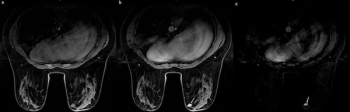

Emerging research showed that AI-generated ADC mapping from MRI led to significant increases in accuracy, PPV and specificity in comparison to conventional ADC mapping while achieving a 93 percent sensitivity for PCa.